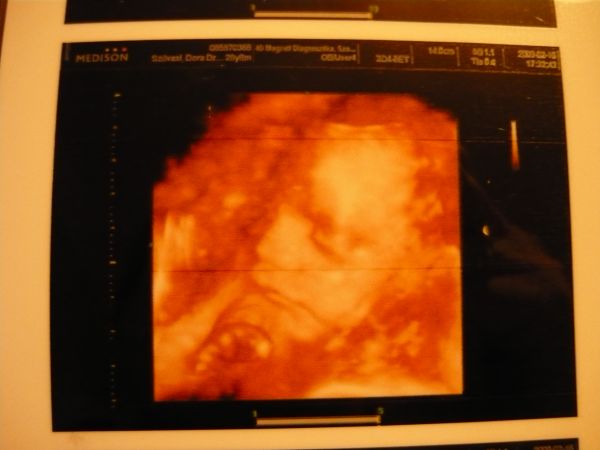

na, a képek, majd még hozok jobbat is, ha el tudom menteni a DVD-ről:

Kép Kistesó

Kép Szabi a 4D-s képen

megvagyunk, minden O.K., KISFIÚ!!!!! :)

Csajok, ekkora hasonlóságot a két fiú közt!!!! Egyrészt milliméterre pontosan egyeznek az adataik (Szabival is 26 hét 2 naposan voltunk, most 26 hét 3 nap)

BPD: 72 mm

THQ: 70 mm

FL: 49 mm

Kilára 1 kiló 10 deka, Szabi 1 kiló 6 deka volt...

De az arca!!!! Petivel összenéztünk, mikor megláttuk: TISZTA SZABOLCS!!!!!!!! :) Olyan édes!